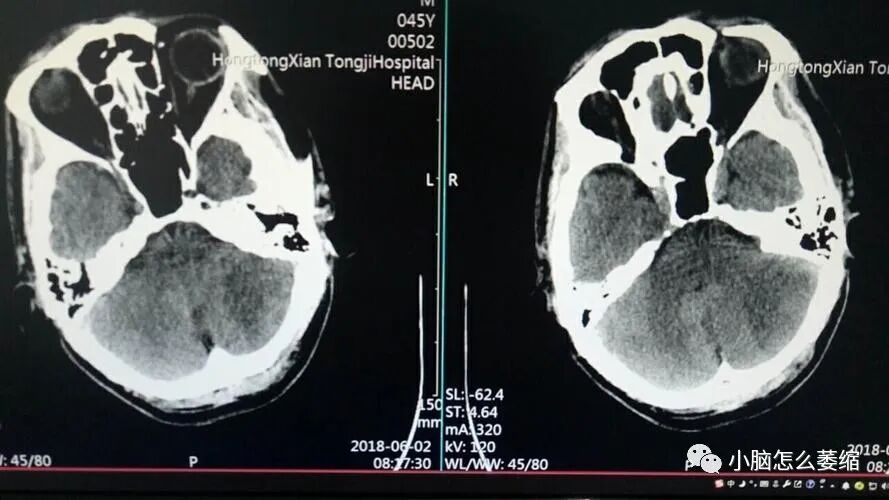

小脑萎缩是一种神经影像学诊断,主要表现为小脑体积缩小、细胞数减少。这种病症常常引起动作协调性丧失、肌张力减退,以及语言和认知能力的减退。在本文中,我们将分享一个采用中药治疗小脑萎缩的成功案例。

患者张先生,今年65岁,患小脑萎缩已有一年。他主要表现为步态不稳、言语不清、以及肌张力减退等症状。在接受西医治疗无明显效果后,他转向中医寻求帮助。后来经以前的病友介绍,得知盛劲强大夫治疗小脑萎缩的效果不错,于是联系盛劲强大夫的预约咨询客服庞海峰,经过简单咨询之后,决定预约盛劲强大夫的面诊号位。盛大夫中医辨证为“痿证”采用补髓健脑汤加减药物治疗。

患者用药三个疗程后,头晕情况近一月没有出现,眼睛看东西不模糊了,耳鸣减轻了,口干口苦基本没有、流口水基本没有了,四肢无力感减轻了,整体的精气神要比用药前好上许多,患者为巩固病情不让其继续发展,甚至抱有好转的心思,继续服用。六个疗程后,症状基本改善,身体有力气了,自己可以适当性地做一些运动,走路比以前稳多了,还在积极治疗中。